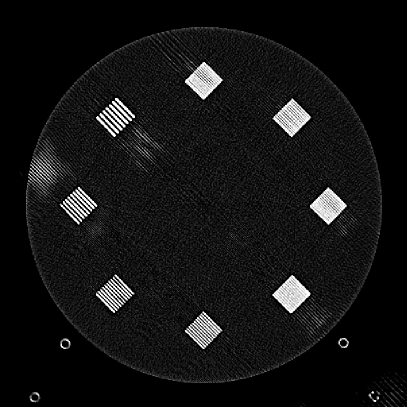

Refer to caption

(a)

(b)

Figure 9: (a) The ACR phantom module 1 with 4 different inserts for CT number fidelity testing. In addition, two ramps of wires are visible near the phantom center. The image display window center is 150 HU and window width is 700 HU. (b) The phantom module 3 with a uniform water-equivalent radiodensity of 0 HU. The display window center is 0 HU and window width is 400 HU.

To evaluate image quality, we first tested the performance of JENG on a standard CT phantom, CT ACR 464 phantom 35. Then we tested JENG on 5 clinical thoracic datasets and 3 abdominal datasets. The ACR 464 phantom contains four modules in total, with each module 40 mm in depth and 200 mm in diameter. The first module has 4 different inserts to test CT number fidelity. In addition, the module contains a series of wires for cross-plane resolution evaluation, shown as white horizontal bars near the center in Fig. 9(a), and are visible in 0.5 mm z-axis increments. The second module tests low contrast resolution, but is not used in this paper. The third module, shown in Fig. 9(b), is a uniform cylinder of water-equivalent material of 0 Hounsfield units (HU), and we used this module to quantitatively measure image noise profile and in-plane resolution. The fourth module consists of resolution bars of various spatial frequencies for analysis on high contrast resolution. To scan the phantom, the scanner setup used dual sources with 2 focal spots at each source. In addition, the projections were acquired using the same protocol for clinical thoracic scans with 100 KV, a nominal tube current of 718 mA and a high helical pitch of 2.8. For all experiments, we compared JENG against the state-of-the-art Siemens ADMIRE, reconstructed with a BL-64 soft tissue sharp kernel, and we define ADMIRE as the clinical standard hybrid IR method for the rest of the paper.